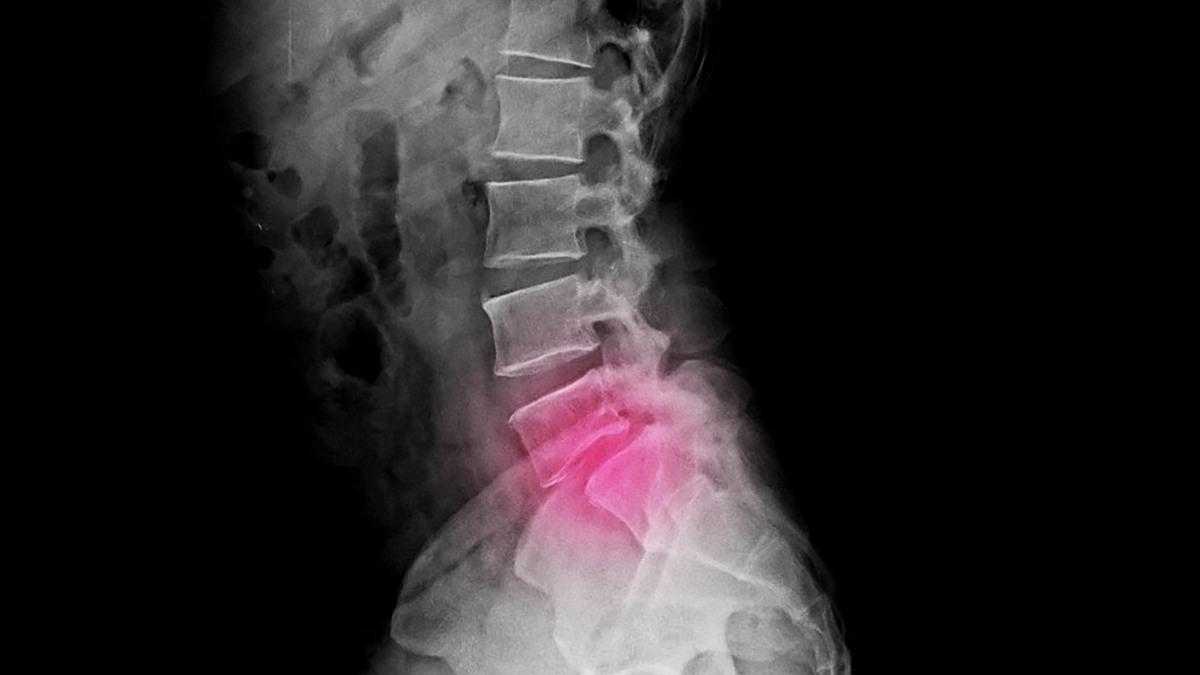

La espondilolistesis “es el desplazamiento de una vértebra hacia delante respecto a la inmediatamente inferior”, explica Miguel Ángel Plasencia, jefe de la unidad de columna de la Clínica Cemtro.

Si hay un fallo en estas apófisis articulares, «el cuerpo vertebral superior no tiene contención y se desplaza hacia adelante. La vértebra se escurre. Esto es la espondilolistesis», describe García de Sola.

El diagnóstico se puede hacer “con una radiografía lumbar convencional que permite detectar el desplazamiento vertebral”, explica Plasencia, ya que, como apunta García de Sola, «en ella se puede ver claramente cómo está una vértebra deslizándose sobre la inferior».